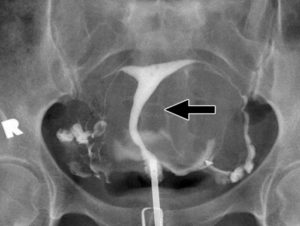

Непроходимостью фаллопиевых труб нарушает продвижения сперматозоидов к яйцеклетке. Она может быть функциональной, в данном случае никаких анатомических изменений не выявляется, но по определенным причинам нарушается функционирование маточных труб, и органической – когда в трубах происходит ряд различного рода изменений, мешающих их проходимости.

Различают частичную и полную непроходимость — гидросальпинкс. В случае частичной — непроходим лишь определенный участок трубы. В случае полной — труба непроходима полностью.